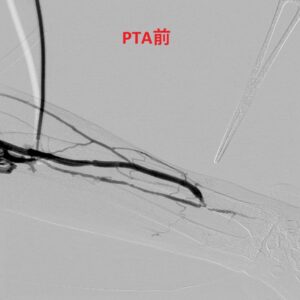

バスキュラーアクセス関連手術(内シャント手術、経皮的血管拡張術(PTA)

しかしそこにはまた新たな問題がありました。そう、シャント手術は非生理的なのでした。そのため(とは断言できませんが)、一度作製しても徐々に静脈内に狭窄が生じ血液量が低下したり、時に完全に閉塞したりすることも当初から稀ならず認められました。小生が医師となり診療を開始した平成2年では、一度作製したシャントが閉塞すればまた違う部位で再作製する以外に方法はありませんでした。しかしこの25年ほど前からは狭窄部を血管内からの細長い風船(長さ4cm程度、幅4〜6mm)で膨らませ血管内膜に亀裂を生じさせることで、今のシャントをより永くもたせうることが可能となりました。いわゆる経皮的血管拡張術(PTA)と言われる手術です。これまで小生もシャント手術1000例以上、PTA700例以上の経験を1歩ずつ積んで参りましたが、少しずつ改良を重ね自分にしかわからないであろう技術を磨いてまいりました。また小生の場合は常に自分で透析管理を行っている患者さんへのみ施行し他院から手術のみという方への対応は行って来なかったこと、手術前後の穿刺も全てスタッフ任せにせず全て自ら直接行い、したがって術後の経過を詳細にフィードバックしてきたこと、それらをより良い手術方法への変遷へ生かしてきたこと、を 僭越ながら自負しております。またPTA手技の延長においては10年ほど前から狭窄部を単に拡張することのみならず、完全に閉塞したシャントを再度復活させることも9割以上の症例で可能となってきたことも福音といえると思われます。手技的には簡単でもあり難しくもあり奥の深い手術ですが(全例日帰り可能、局所麻酔のみ、所要時間:30分〜1時間前後)、拡張しすぎない、ほどほどの拡張の方が結果が良いという印象があり、今後も必要な患者さんへは過不足なくほど良いタイミングで施行し、今後も精進を積み重ねて参りたいと思っています。